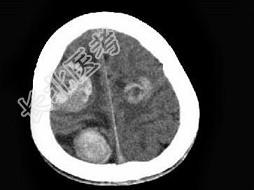

- 单项选择题男,22岁, 耳后见一直径约2cm黑痣,表现有溃烂, 近期增大明显,头痛1周, 伴咳嗽、胸闷,行头颅CT及MRI检查见颅内多发病灶, 最可能的诊断为 ( )

A、黑色素瘤脑转移